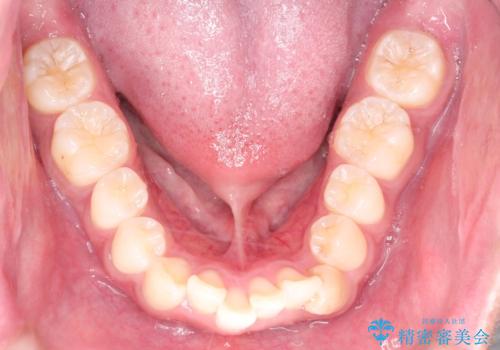

インビザラインによる出っ歯の矯正

- 出っ歯と下の歯のガタガタを主訴に来院されました。

上の奥歯を後方に移動させて、スペースを作り前歯を内側に引っ込める計画としました。

インビザラインによるマウスピース矯正で治療をすることとしました。

インビザラインをしっかり使用していただいたので、スムーズに治療をおえることができました。